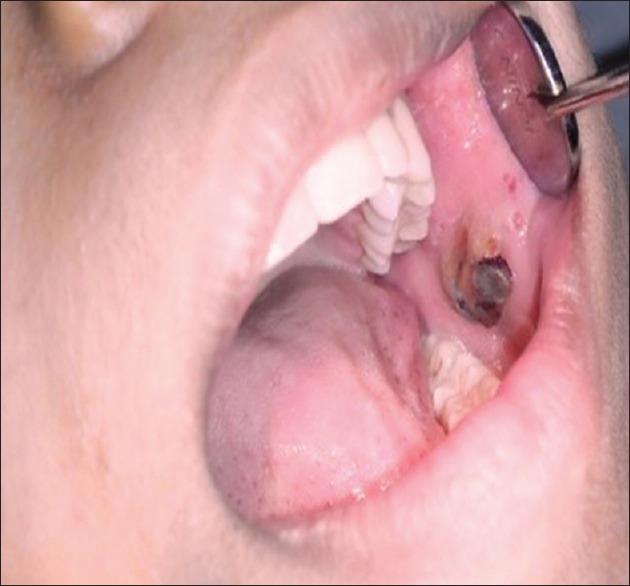

颊黏膜血管淋巴管瘤:1例罕见病例报告

Hemangiolymphangioma of buccal mucosa: A rare case report.

Vascular anomalies are mainly classified under two headings, i.e. under vascular tumors and vascular malformations. Hemangioma and lymphangioma are examples for such a vascular anomalies. Malformations may be seen in different combinations of vascular elements, and histologically these vessels may be filled with blood and named lymphangiohemangioma or hemangiolymphangioma according to the dominant tissue structure present. It is a rare developmental anomaly. This paper reports a case of lymphangiohemangioma in a 21-year-old female patient.

摘要

血管异常主要分为两大类,即血管肿瘤和血管畸形。血管瘤和淋巴管瘤就是这类血管异常的例子。畸形可能以不同的血管成分组合出现,从组织学上看,这些血管可能充满血液,并根据主要存在的组织结构被命名为淋巴管血管瘤或血管淋巴管瘤。这是一种罕见的发育异常。本文报告一例21岁女性患者的淋巴管血管瘤病例。